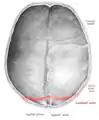

Lambdoid suture (labeled at bottom right)

The lambdoid suture (or lambdoidal suture) is a dense, fibrous connective tissue joint on the posterior aspect of the skull that connects the parietal bones with the occipital bone. It is continuous with the occipitomastoid suture.

The lambdoid suture is between the paired parietal bones and the occipital bone of the skull. It runs from the asterion on each side.

The lambdoid suture is named due to its uppercase lambda-like shape.